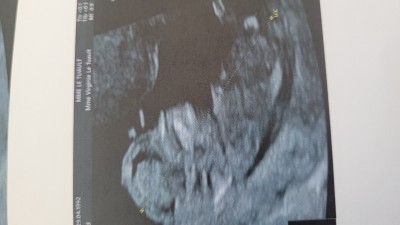

Gebelik haftası 10 haftalik gebelik

Bebegin kafasına bakınca sanki erkek gibi görünüyor. Erkeğe benzettim :)